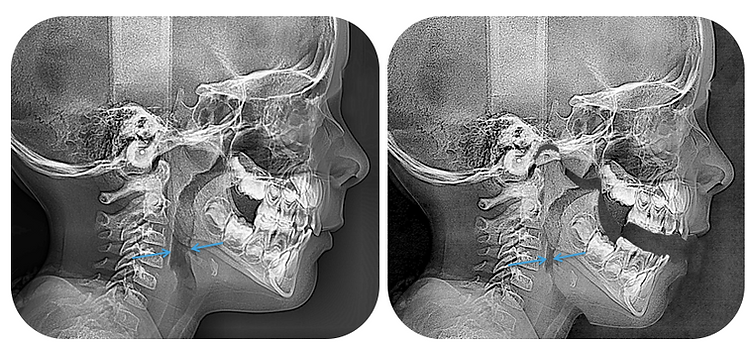

Pictured here are 2 different types of scans to show the effects of mouth breathing on the airway. Opening the mouth 1/2 inch causes the oropharynx (or the upper part of the airway) to be reduced by 6mm

Effects of mouth breathing on airway CBCT scan showing compromised airway

As a frame of reference, the average 7 year old child should have an airway that is approximately 7mm anteroposteriorly. So when a child of that age is breathing through his or her mouth, it's comparable to having their airway reduced to the size of a coffee straw.

For adults, a healthy airway can be measured within a range of 11-15mm.